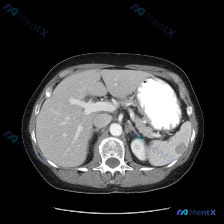

今天整理了一份上腹部增强CT的病例,关于脾脏结节的读片和鉴别思路,分享一下: 先看完整影像表现 这是一张上腹部增强CT横断面(软组织窗),对比剂显影良好,主要观察到两个核心异常: 1. 肝脏:肝左外叶、右后叶各见一个类圆形低密度灶,边界清、无强化,符合典型肝囊肿表现; 2. 脾脏:脾实质内见一个类圆...